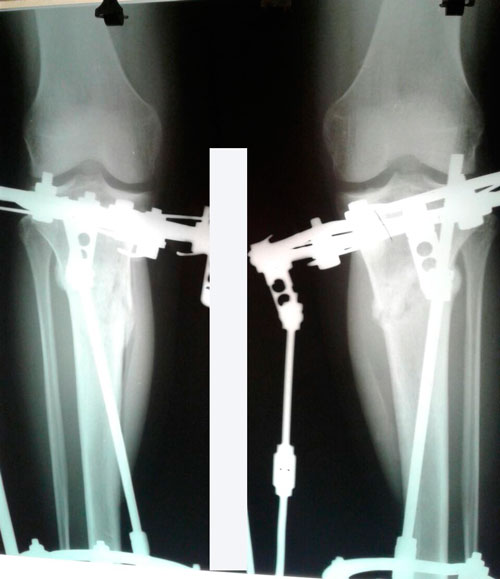

в процессе исправления ротации.

Обратите внимания на стопы, (в покое) они уже не заваливаются.